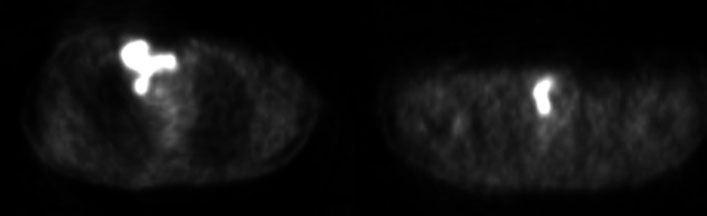

Fourteen years later, the patient presented to our institution with a palpable cervical mass. A total body CT revealed a non-enhancing diffusely enlarged hypodense thyroid gland without the presence of enlarged lymph nodes or other significant abnormalities (Figure 3). A magnetic resonance (MR) examination of the neck done one month later showed a rapid increase in size of the thyroid gland demonstrating diffuse enhancement postgadolinium administration and restricted diffusion. It showed to exert mass effect on the surrounding structures and significant narrowing of the airways. No pathological lymph nodes were seen (Figure 4, Figure 5, Figure 6). Because of the patient’s previous history of lymphoma and rapid growth of the thyroid gland, the possibility of extra-nodal thyroid lymphoma recurrence was raised, and a core needle biopsy of the thyroid gland was done and sent to pathology which confirmed the presence of diffuse large B-cell lymphoma within the thyroid gland.

Figure 6: Sagittal DWI and ADC MR images (2025) showing a diffusely enlarged thyroid gland demonstrating restricted diffusion.